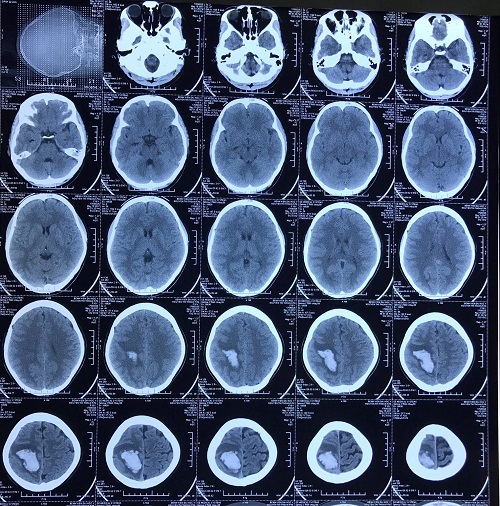

Đau đầu uống giảm đau, cô gái trẻ Hà Nội bất ngờ hôn mê

Sau vài tháng đau đầu dai dẳng, tự uống thuốc giảm đau nhưng không đỡ, cô gái trẻ ở Hà Nội bất ngờ rơi vào hôn mê.

Chủ quan với cơn đau đầu, cô gái trẻ rơi vào hôn mê vì đột quỵ

- Nghĩ còn trẻ, khi bị đau đầu Hoa tự ý mua thuốc giảm đau uống, tuy nhiên sau đó cơn đau tăng lên, uống thuốc không tác dụng.